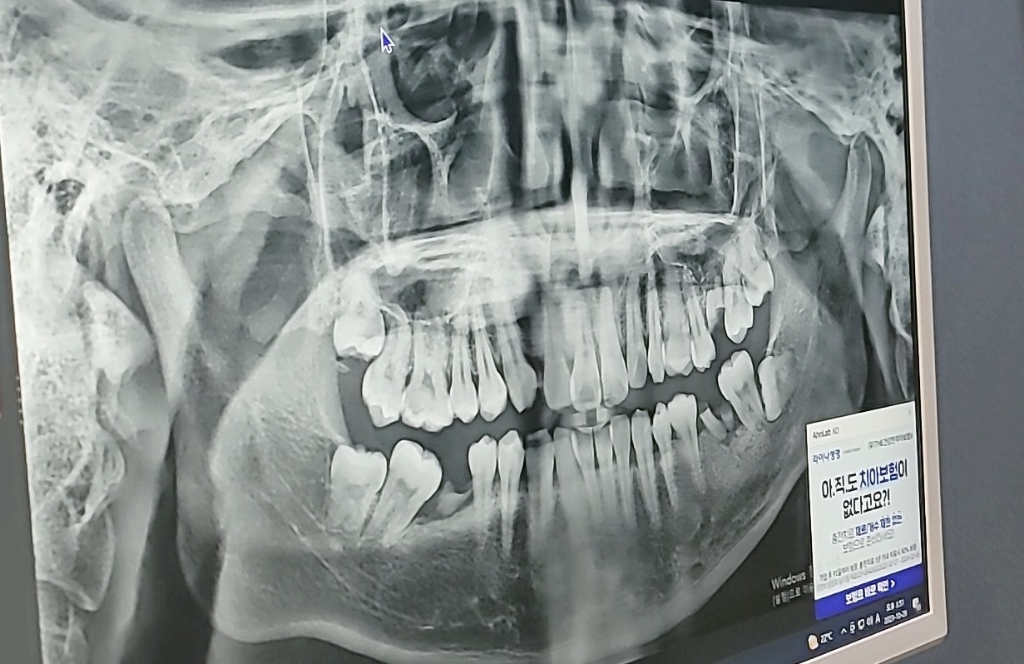

사진으로 봤을 경우 오랜 기간 치아가 없다가 보니 치열이 어긋난 것으로 보입니다.

치주가 안 좋지 않은 뽑는 것이 좋고 치아가 없는 부위는 인플란트 나 보철치료를 해서 수복을 해 주는 것이 좋습니다.

치아가 엄청 안 좋은 것은 아니니 치료를 잘 받아서 그리고 관리를 잘해서 오랫동안 사용 하는 것이 좋습니다.

뿌리만 남은 치아는 의미가 없으니 정리하고 임플란트를 심고, 치료가 필요한 부분의 치아에 대해서는 치료를 하시면 될 것 같습니다

부러진 치아, 충치도 문제지만 나이대에 비해 잇몸뼈의 상태가 안 좋아 보입니다. 잇몸치료도 동반되어야 할 것 같습니다